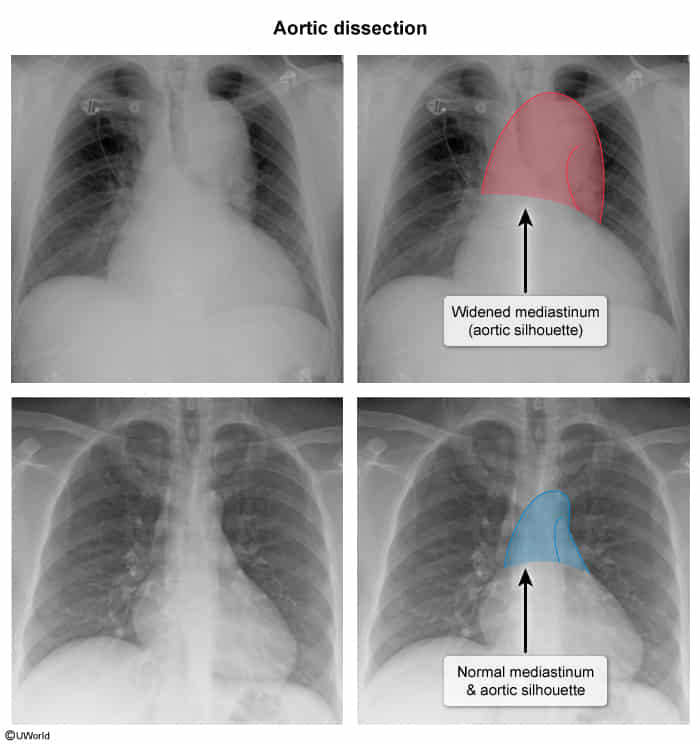

• Chest X-ray (CXR): Often the first imaging study; may show a widened mediastinum (>8 cm).